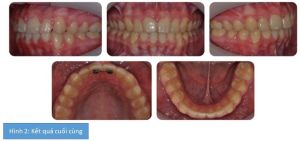

Kết quả cuối cùng được thể hiện ở hình 2